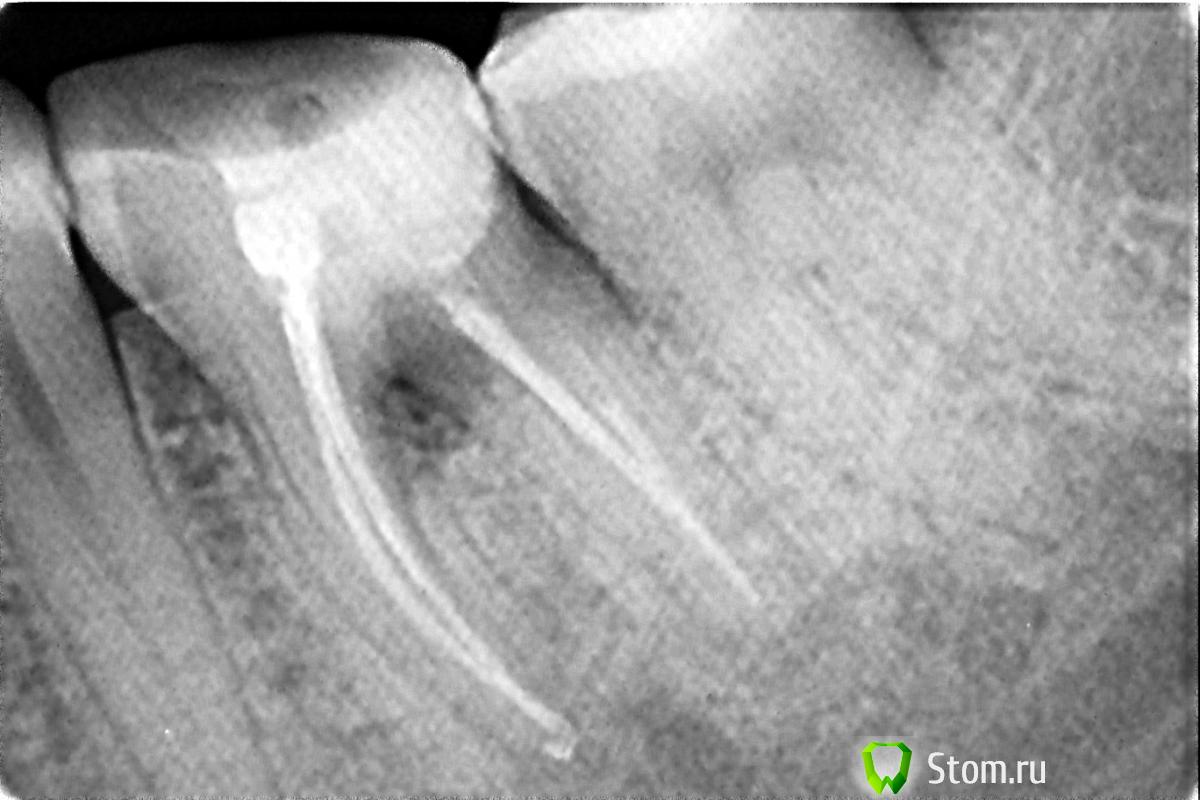

pho Опубликовано 2 апреля, 2012 Поделиться Опубликовано 2 апреля, 2012 (изменено) Добрый день! Мне 35 лет. Два года назад заболел зуб. В течении месяца ныло, под конец уже с сильной болью обратилась к врачу. Вскрыли пломбу, под пломбой оказался кариес. Удалили нервы, запломбировали каналы( а их оказалось 4 шт). Лечение стоило аж 8000руб. Через 2 месяца обнаружила свищ на десне этого зуба. Ничего не беспокоило. Сделала снимок(прилагается) . Затемнение между корней. В клинике где делали рекомендовали удалить . В других -наблюдать. Вопрос почему это случилось? Год спустя снимок показал без изменений, Недавно снова сделала снимок- тоже без изменени, свищ закрылся. Но сейчас уже 3 день как побаливает при нажатии. Что делать? Возможно ли в моем случае сделать коронко-радикулярную сепарацию, т. е разделить зуб на две части и провести соответствующую терапию? Изменено 2 апреля, 2012 пользователем pho Ссылка на комментарий